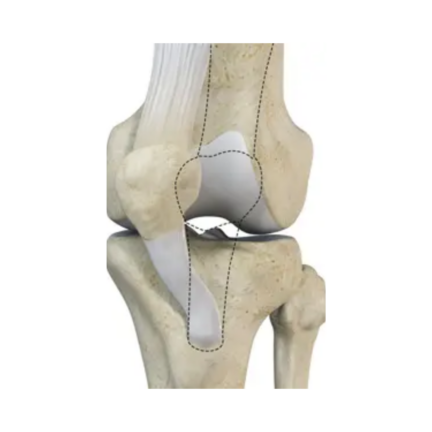

Knee Problem

Knee Arthritis

Knee Preservation

Pattela Dislocation

Total Knee Replacement (TKR) Package – Implant Based Cost Guide